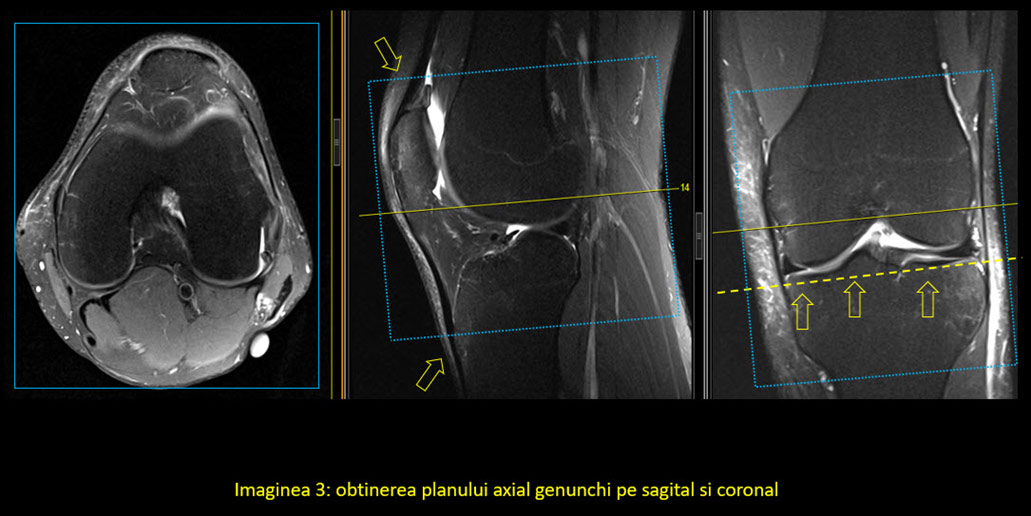

În mod normal, planurile uzual utilizate în imagistică sunt coronal, sagital și axial. În cazul genunchiului și majorității articulațiilor, oasele și articulațiile au o orientare specială, astfel încât se folosesc planuri modificate. Singurul plan standard este cel axial, deși poate suferi și el modificări în anumite condiții.